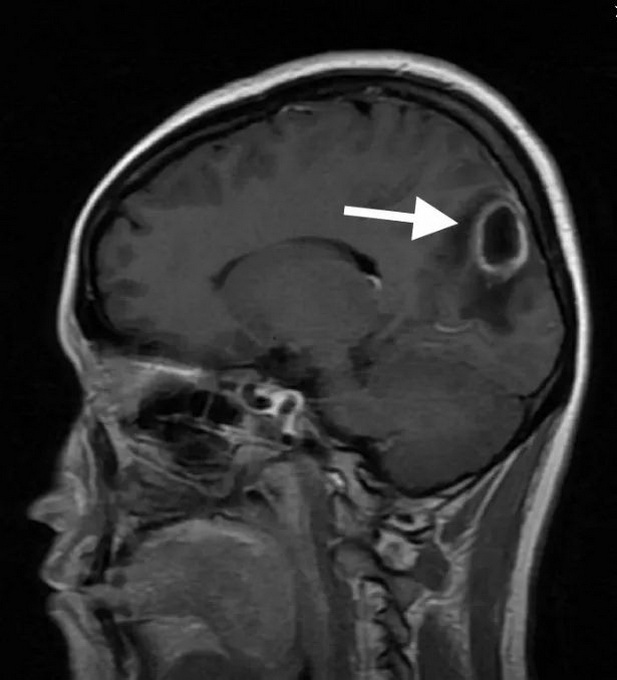

极为凶险年轻妈妈发现脑子里一个圆圆的病灶小鱼(化名)是一位28岁的年轻女性 , 有个3岁的女儿 , 一家人生活其乐融融 。 1个月前 , 小鱼开始出现头痛、头晕的症状 , 并且症状越来越重 。 家人陪她到当地医院检查 , 头颅CT和磁共振发现小鱼的大脑里藏着一个圆圆的病灶。 医生说 , 可能需要开颅手术 , 这可把大家吓坏了 , 听说浙大二院神经外科省内最好 , 小鱼和家人很快慕名而来 。 ![]()

小鱼脑内的脑脓肿接诊的神经外科林邵奇医师详细询问了病史 , 查看了小鱼的磁共振片子 , 并向主管的陈景森副主任医师和严锋副主任医师汇报病情 。 “从片子上看 , 小鱼的大脑里确实潜伏着一个圆圆的病灶 , ”陈景森说 , “她得的是脑脓肿 , 这种疾病就像在人的大脑里面裹了一包脓液 , 十分凶险! ”

“从小鱼的片子上看 , 病灶体积大 , 周围还伴有严重的脑水肿 , 需要开颅手术切除病灶 , ”严锋副主任医师说 , “但是这个脑脓肿的始作俑者到底是什么 , 还是一桩“悬案” 。 ”